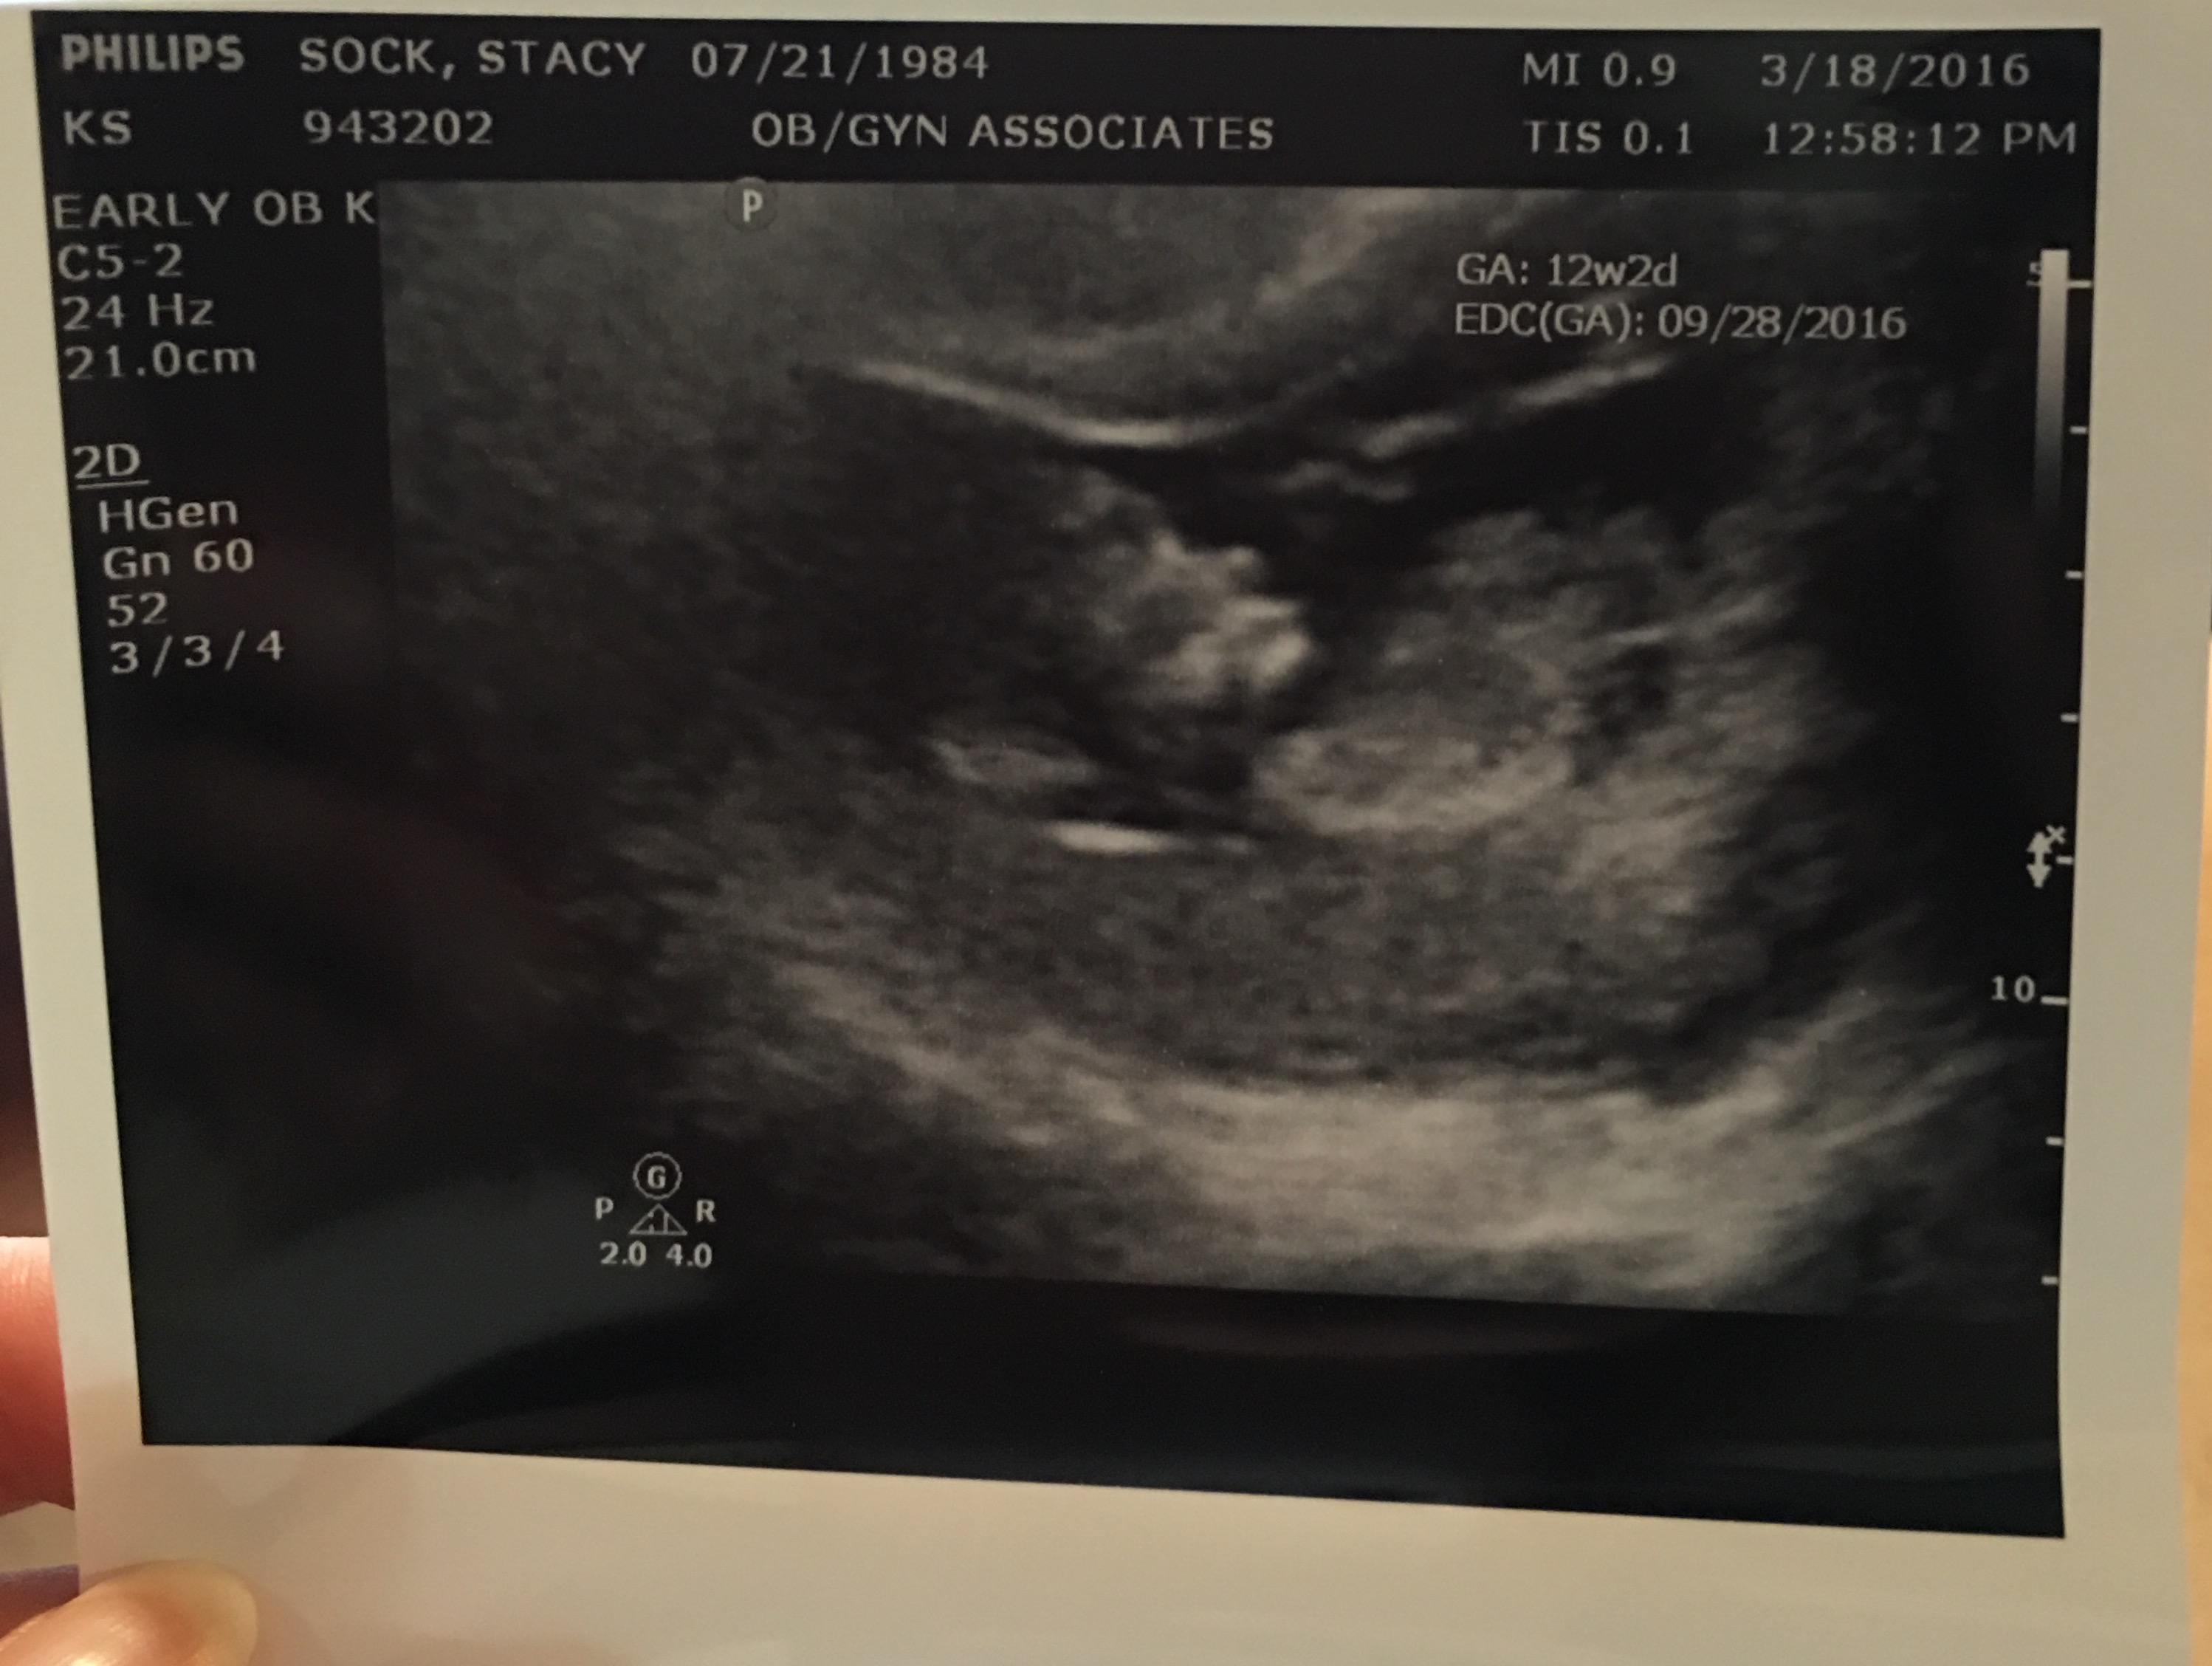

How far along? 12 weeks.

Best moment the week: Having Bobby home and going to see the baby again on the ultrasound. Growing just perfect with a HR of 154. I still think it’s a boy and the nose is a “Sock nose” that’s for sure.